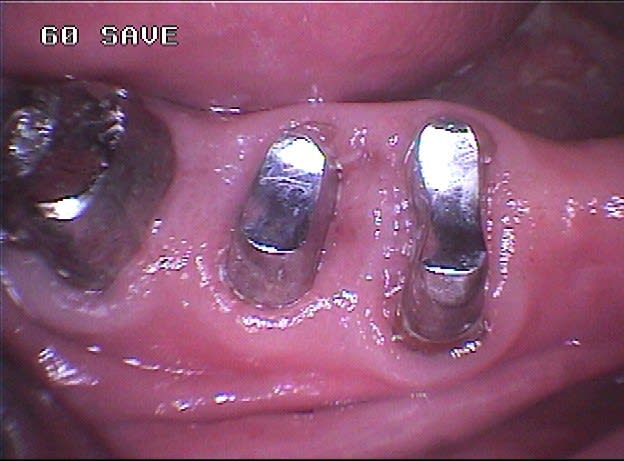

Quoi, des inlay cores métalliques ? Scandale !

J'envisage de tester des inlaycores céromères réalisés au labo avec tenon en quartz et même clavettés pour des unitaires mais je ne me risquerai pas encore à les utiliser comme piliers de bridge. J'ai déjà réalisé un inlaycore en emax/quartz en indirect pour une antérieure, le résultat est top mais l'assemblage reste assez délicat.

Les couronnes céramiques sur CoCr étant réalisées sans bandeaux métalliques et les racines étant sensées être étanches, une structure métallique intermédiaire scellée n'a aucun impact galvanique ni esthétique.